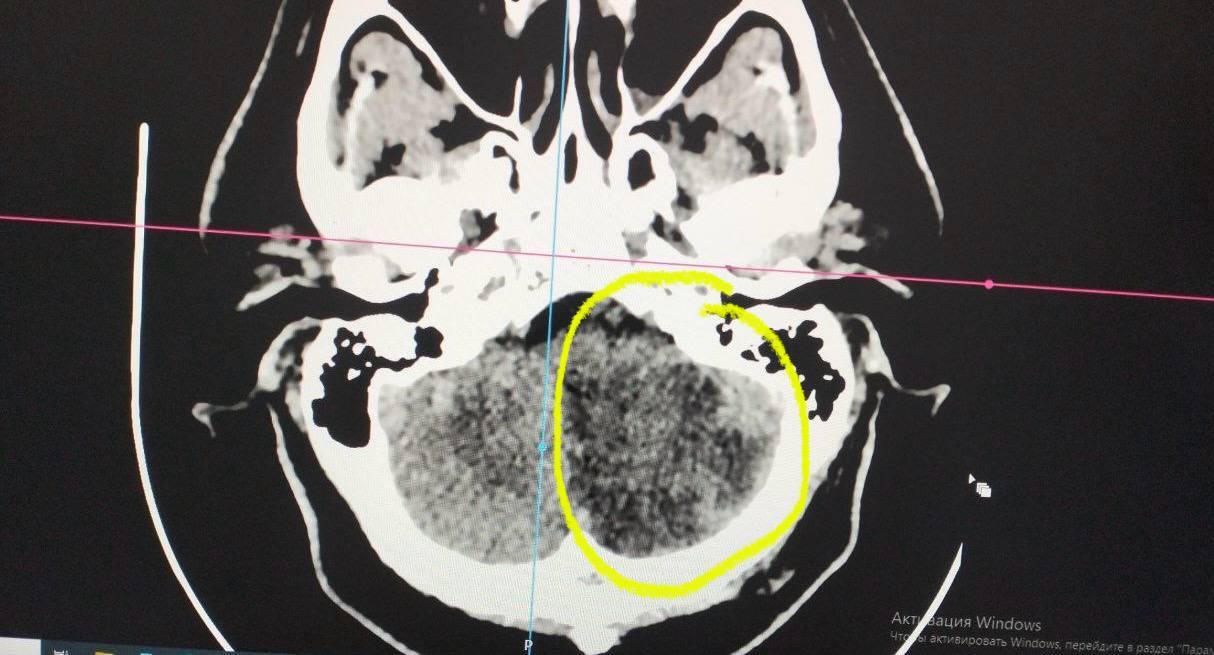

Диагноз: обширный ишемический инсульт левого полушария мозжечка.

"Случай уникален тем, что пациент, имея поражение целого полушария мозжечка, вернулся к полноценной жизни", – отмечает заведующая ПСО №2 Наталия Холмова.